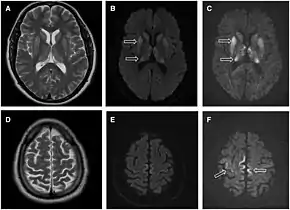

Imaging of the brain may be performed during medical evaluation, both to rule out other causes and to obtain supportive evidence for diagnosis. Imaging findings are variable in their appearance, and also variable in sensitivity and specificity.[41] While imaging plays a lesser role in diagnosis of CJD,[42] characteristic findings on brain MRI in some cases may precede onset of clinical manifestations.[43]

Brain MRI is the most useful imaging modality for changes related to CJD. Of the MRI sequences, diffuse-weighted imaging sequences are most sensitive. Characteristic findings are as follows:

- Focal or diffuse diffusion-restriction involving the cerebral cortex and/or basal ganglia. In about 24% of cases DWI shows only cortical hyperintensity; in 68%, cortical and subcortical abnormalities; and in 5%, only subcortical anomalies.[44] The most iconic and striking cortical abnormality has been called "cortical ribboning" or "cortical ribbon sign" due to hyperintensities resembling ribbons appearing in the cortex on MRI.[45] The involvement of the thalamus can be found in sCJD, is even stronger and constant in vCJD.[46]

- Varying degree of symmetric T2 hyperintense signal changes in the basal ganglia (i.e., caudate and putamen), and to a lesser extent globus pallidus and occipital cortex.[42]

- Cerebellar atrophy